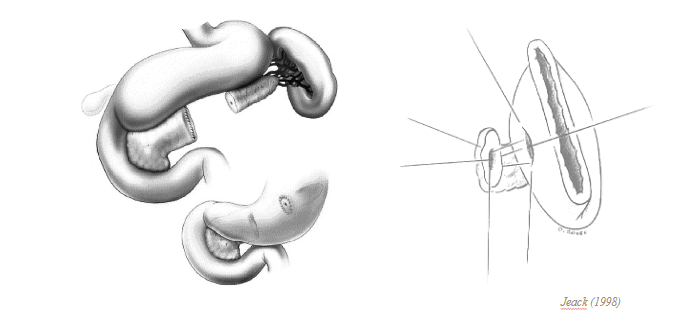

Kỹ thuật 3 ống thông giảm áp lực tá tràng – Duodenal decompression with triple- tube intubation

- Mở thông dạ dày

- Dẫn lưu tá tràng qua mở thông hỗng tràng

- Mở thông hỗng tràng nuôi dưỡng

- Dẫn lưu rộng rãi vùng tá tràng, đầu tụy